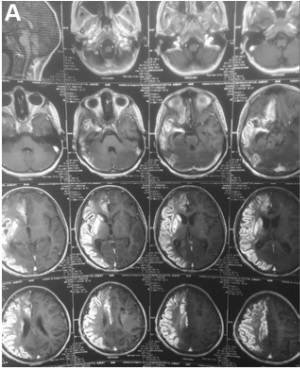

然后,患者被转移到利马一个更高级的神经中心治疗,在那里接受进一步的诊断。脑CT和MRI显示右侧大脑中动脉和右侧大脑前动脉区域存在急性缺血。DSA显示双侧颈内动脉完全闭塞,右侧为眼动脉远端,左侧为后交通动脉远端,双侧基底节呈“烟雾”络脉改变,右后交通动脉通畅,然而没有明显的侧支循环,是来自右颈外动脉的侧支循环(图1)。

▼图1术前脑MRI(A)显示右侧大脑中动脉和右侧大脑前动脉区域急性缺血。

术前DSA显示双侧颈内动脉、右侧眼动脉远端和后交通动脉远端完全闭塞,双侧基底节烟雾络脉(B,左颈内动脉和颈外动脉分支;C,右颈内动脉和颈外动脉分支)。